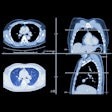

Avicenna.AI launches pulmonary embolism program